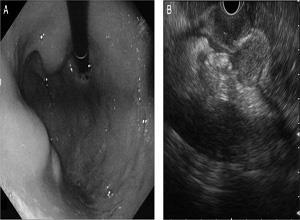

胃结核

简介胃结核是人体各器官结核感染中最罕见的一种,Benjamin(1933)仅能从世界文献中搜集得225例,而Good在7416例胃手术中仅有3例胃结核病,可见该病是非常罕见的,晚期结核病人患肠结核者颇多而患胃结核者如此之少,其机制不明,或者与胃的杀菌力和胃壁缺乏淋巴滤泡有关。